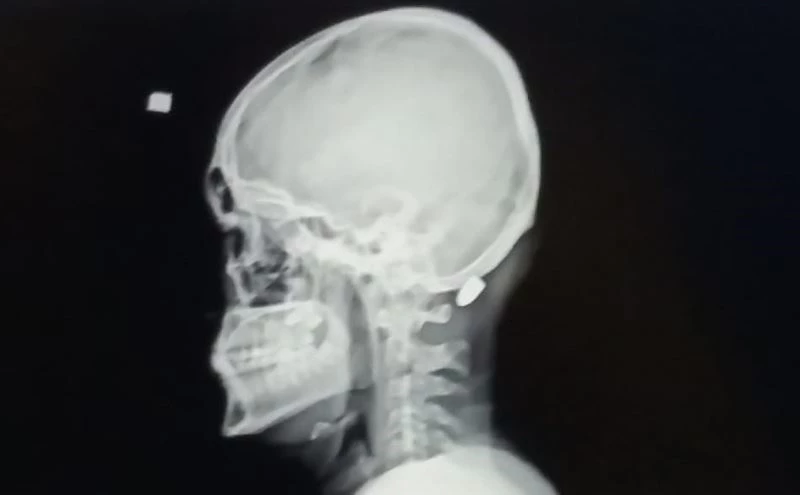

Trabzon’un Vakfıkebir ilçesindeki Karadağ Yaylası’nda bir evin dış cephe kaplamasını yapan 18 yaşındaki Ali Kuleyin’in başına nerden atıldığı belli olmayan kurşun isabet etmiş, ilk önce kurşun olduğunu anlamayan genç, elini başına götürdüğünde kan geldiğini anlayınca hastaneye kaldırılmıştı. İsabet eden yorgun mermi başarılı bir operasyonla saplandığı yerden çıkartılmıştı.